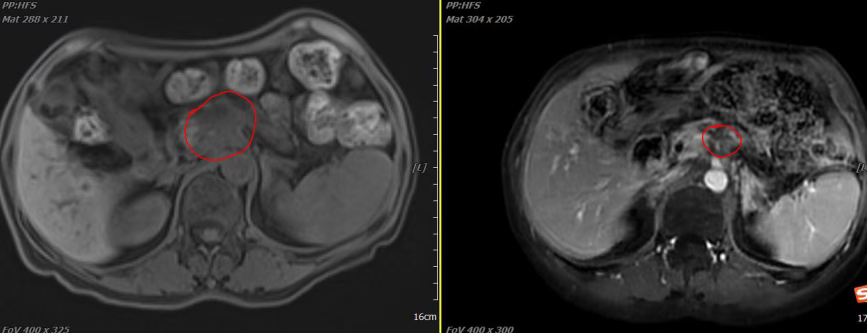

Case 1: Patient Su with Malignant Tumor of the Pancreatic Body

Brief Medical History: Patient Su, female, 59 years old, admitted primarily due to "discovery of pancreatic cancer 4 months ago, after 6 cycles of chemotherapy." Abdominal MRI from The First Hospital of Shanxi Medical University in January 2025 showed: Hypovascular occupying lesion in the pancreatic body (5.1*4.1cm), accompanied by atrophy of the pancreatic body and tail, mild dilation of the pancreatic duct. The lesion encased the main portal vein, celiac trunk, and superior mesenteric artery, with compression and narrowing of the celiac trunk, leading to occlusion of the portal vein and splenic vein with collateral circulation formation. Considered pancreatic cancer, possibly accompanied by metastasis to the left side of the portal vein and retroperitoneal lymph nodes. Subsequently, endoscopic ultrasound-guided pancreatic mass biopsy was performed: (Pancreas) Microscopic examination of submitted tissue showed hemorrhage and inflammatory exudate, with only scattered, very few glands showing mild atypia. Please correlate clinically and resubmit if necessary. Pathology consultation at Shanxi Provincial Cancer Hospital: (Pancreatic mass) Puncture: Fragmented glands seen in inflammatory exudate. Pathological diagnosis from Fudan University Shanghai Cancer Center (Pathology E2025-00115) on 2025-01-20: Aden epithelial cells seen, some cells with moderate to high-grade atypia, along with scattered abnormal cells and inflammatory necrosis, suggestive of adenocarcinoma. After definitive diagnosis, the patient was treated at our hospital. Carbon ion radiotherapy for malignant tumor of the pancreatic body began on 2025-06-12, with total dose: PTV: 41.4Gy(RBE)/9Fx, PTVboost: 13.8Gy(RBE)/3Fx. Concurrent chemotherapy with "Gemcitabine (1000mg/m²) intravenous drip, days 1, 8, 15, Q4W" was initiated on 2025-06-13.

2. Imaging Comparison

2025-05-30 2025-10-16